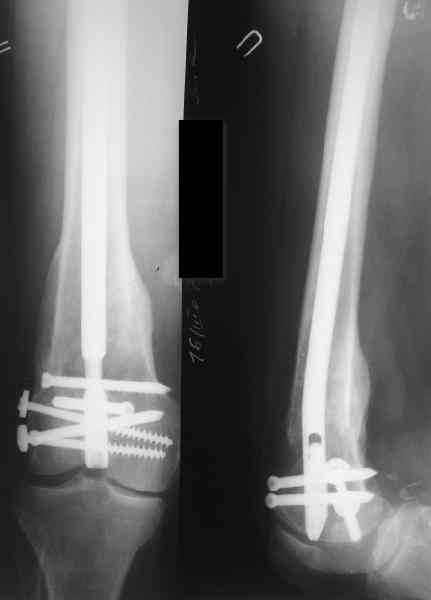

В приложении пример, дистальный отломок пружинил кзади. Два винта потому, что первый оказался чуть кпереди и не упирался в гвоздь.